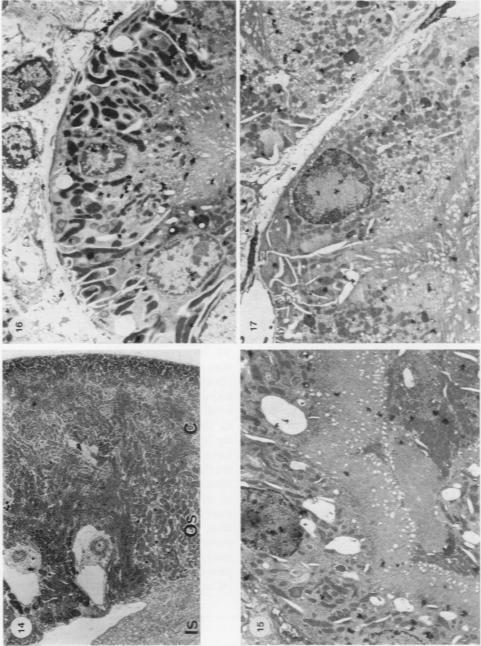

In JCLR and Wistar-Porton rats renal concentrations of Cd2+ were maximal (21-22 micrograms Cd2+/g wet wt tissue) at 1 and 4 h respectively after the administration of CdCl2 (10 micromol, 1-12 mg Cd2+/kg body wt) together with L-cysteine (5 mmol/kg body wt). Synthesis of metallothionein in the kidney in response to the uptake of Cd2+, which occurred between 2 and 7 h after treatment in the Wistar-Porton rat, affected the distribution of Cd2+ between proteins of the renal soluble fraction, but not between the particulate components and, at both times, about 40% of the total Cd2+ was associated with the heterogeneous nuclei + cell debris fraction. Autoradiographic studies with 109CdCl2 revealed that Cd2+, accumulated by the kidney under these conditions, was not uniformly distributed throughout the renal cortex, but was concentrated unevenly in proximal tubules in the outer stripe of the outer zone of the medulla. Pathological changes, which were correlated with the concentrations of accumulated Cd2+ and were limited to the S3 segments of the proximal tubules, were apparent by light microscopy at 4 h after the administration of Cd2+ + cysteine and progressed with time. Thus by 7 h the lesion had extended to include almost the whole of the outer stripe of the outer zone of the medulla and, by 24 h the cells of the affected epithelia showed extensive necrosis and karyorrhexis. At this, as at earlier times, the cortex appeared to be undamaged. Neither these nor other morphological changes were observed in the kidneys of animals that had been dosed with either Cd2+, or L-cysteine alone. Within 60 min of the administration of Cd2+ + cysteine an increase in the number of endocytotic vesicles in the apical cytoplasm of the proximal tubular epithelium was observed by electron microscopy. Subsequent cytoplasmic vesiculation, which was conspicuous at 2 h, was extensive and widespread in both the apical and basal regions of the cytoplasm at 4 h. In some cells at this time the nuclei were irregular in shape; the mitochondria were swollen and their cristae were disorganized. As, after the administration of either Cd2+ or cadmium-metallothionein, damage is known to occur in the S1 and S2 segments of proximal tubules throughout the cortex, the Cd2+ + cysteine combination does not provide an exact model which reproduces in a short time the effects of long-term, low level exposure to Cd2+. Nevertheless it is suggested that the toxic mechanisms are the same after either treatment with Cd2+ + cysteine or continual exposure to Cd2+, but are limited to different segments of the proximal tubules. Possible mechanisms of toxicity are discussed.

在JCLR大鼠和Wistar-Porton大鼠中,在给予氯化镉(10微摩尔,1-12毫克镉离子/千克体重)和L-半胱氨酸(5毫摩尔/千克体重)后,肾脏中镉离子的浓度分别在1小时和4小时达到最大值(21-22微克镉离子/克湿重组织)。在Wistar-Porton大鼠中,处理后2至7小时内,肾脏中因摄取镉离子而合成的金属硫蛋白影响了镉离子在肾脏可溶性部分蛋白质之间的分布,但不影响颗粒成分之间的分布,并且在这两个时间点,总镉离子的约40%与异质核+细胞碎片部分相关。用109氯化镉进行的放射自显影研究表明,在这些条件下肾脏积累的镉离子并非均匀分布于整个肾皮质,而是不均匀地集中在髓质外带外层的近端小管中。与积累的镉离子浓度相关且局限于近端小管S3段的病理变化,在给予镉离子+半胱氨酸后4小时通过光学显微镜可见,并随时间进展。因此,到7小时时,病变已扩展至几乎包括髓质外带外层的全部,到24小时时,受影响上皮细胞出现广泛坏死和核碎裂。此时,如同早期一样,皮质似乎未受损伤。单独给予镉离子或L-半胱氨酸的动物肾脏中未观察到这些或其他形态学变化。在给予镉离子+半胱氨酸后60分钟内,通过电子显微镜观察到近端小管上皮细胞顶端细胞质内吞小泡数量增加。随后的细胞质空泡化在2小时时明显,在4小时时在细胞质的顶端和基部区域广泛且普遍存在。此时在一些细胞中,细胞核形状不规则;线粒体肿胀且嵴紊乱。由于已知在给予镉离子或镉-金属硫蛋白后,整个皮质近端小管的S1和S2段会发生损伤,镉离子+半胱氨酸组合并不能提供一个能在短时间内重现长期低水平接触镉离子影响的精确模型。然而,有人认为,用镉离子+半胱氨酸处理或持续接触镉离子后的毒性机制相同,但局限于近端小管的不同段。文中讨论了可能的毒性机制。